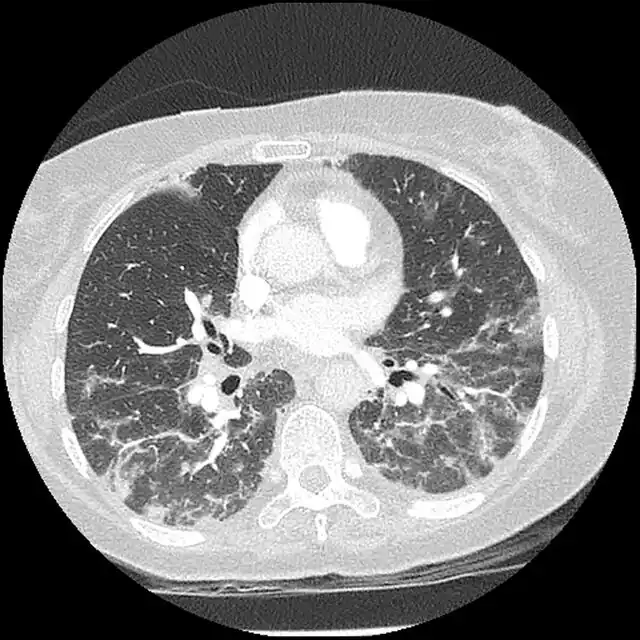

- Imaging such as High Resolution computed tomography [9]

In certain situations, testing of other antibodies, specific imaging (MRI, thoracic high resolution computed tomography), and swallowing evaluation may be needed.